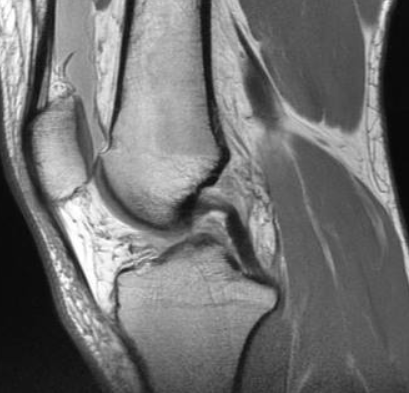

안녕하세요. 오늘은 MRI 건강보험 적용에 대해서 알아보겠습니다. MRI는 꼭필요한 검사이지만 검사비용이 엄청비싸 경제적 부담을 느끼신분들이 많으실겁니다. 하지만 건강보험공단의 보장성 강화에 따라 MRI의 일부 부위에서도 필요시 건강보험 적용이 가능하다고 알려져 있습니다. 저와 함께 하나씩 알아보도록 합시다.

국민건강보험에서는 보장성강화를 위해 이전부터 mri를 건강보험 적용을 위해 바꾸고 있습니다. 년도별로 적용기준이 달랐는데요. 하나씩 설명드리겠습니다.

MRI 건강보험 적용